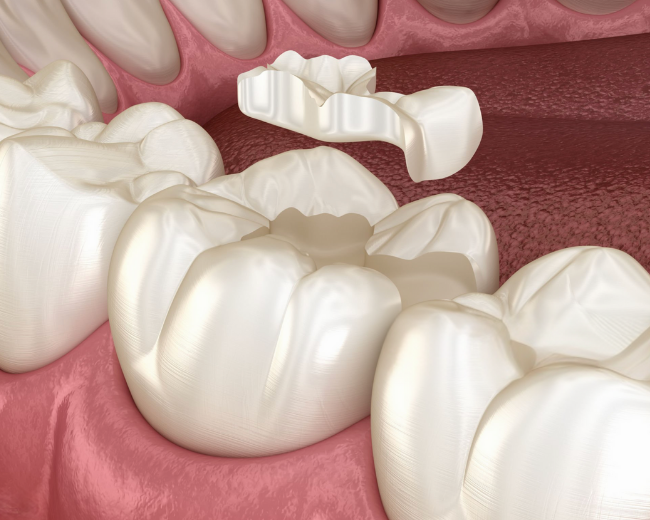

Inlay – Onlay céramique

Une Alternative Moderne et Esthétique qui respecte Votre Dent Naturelle.

Les inlays et onlays en céramique sont des restaurations dentaires sur mesure, idéales pour réparer une dent abîmée sans avoir recours à une couronne complète. Collés directement sur la dent, ils permettent de reconstituer la partie manquante de manière précise, durable et esthétique. Grâce à la céramique, ils se fondent parfaitement dans la dentition naturelle, offrant une solution à la fois discrète, résistante et respectueuse de la structure dentaire.